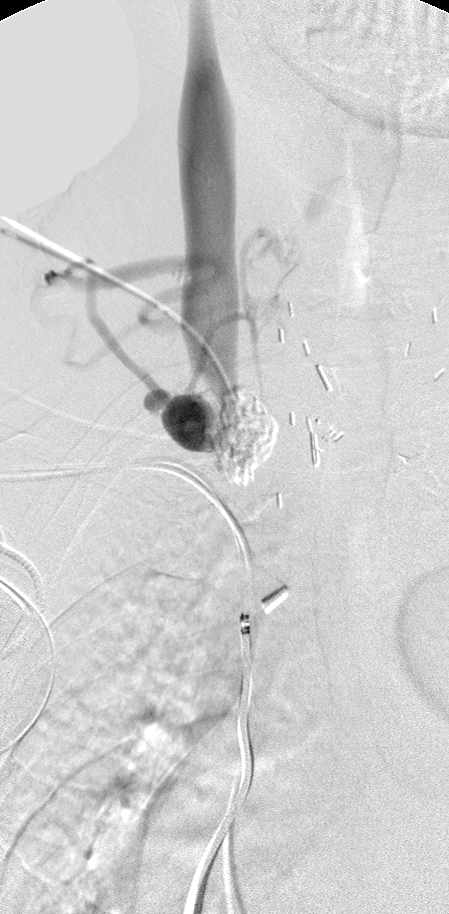

Published July 24, 2014 at 449 × 914 in Hemodialysis Access, Case 6. Ken U. Ekechukwu, MD, MPH, FACP..

Central venogram through the RIJV: There is chronic total occlusion of the distal RIJV.